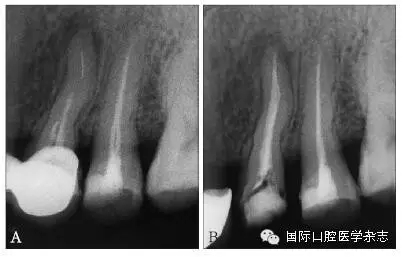

3.2.1 牙本質(zhì)厚度評估 取出分離器械需要損失部分牙本質(zhì),牙本質(zhì)的損失量包括縱向損失和橫向損失??v向損失決定于取出時(shí)分離器械冠方末端需要暴露的長度,橫向損失決定于分離器械的斷端直徑以及選用取出器械的方法(如超聲法或是環(huán)鉆法等)。牙本質(zhì)損失量過多會(huì)導(dǎo)致根管穿孔、根管折斷等并發(fā)癥[7](圖3)。

A:紅色及綠色的部分分別表示用改良GG鉆及超聲工作尖去除牙本質(zhì)的量;B:MicroCT掃描圖像顯示取出下頜第一磨牙近頰根管中分離器械后,導(dǎo)致了根管穿孔。

圖 3 取分離器械過程中會(huì)導(dǎo)致牙本質(zhì)損失,甚至穿孔等并發(fā)癥

目前,對于分離器械周圍牙本質(zhì)厚度的評估以及取出后殘余牙本質(zhì)厚度的預(yù)測主要需借助影像學(xué)檢查,例如根尖片、錐形束CT(cone beamcomputed tomography,CBCT)圖像等。傳統(tǒng)的平行投照的根尖片無法反映三維立體結(jié)構(gòu),且往往存在解剖結(jié)構(gòu)影像的重疊,不利于臨床判斷,具有一定的局限性。多位學(xué)者[10]的研究表明:平行投照的根尖片會(huì)高估實(shí)際的牙本質(zhì)壁的厚度。一些學(xué)者[11-12]的研究表明:當(dāng)分離器械位于上頜第一磨牙近中根管時(shí),采用成角投照(21°)的拍攝技術(shù)與平行投照技術(shù)得到的X線片相比,能更準(zhǔn)確地評估牙本質(zhì)的厚度,為分離器械取出與否提供指導(dǎo)(圖4)。近年來,CBCT在牙髓病學(xué)中的應(yīng)用越來越廣泛,由于CBCT能清楚地反映牙及牙根周圍組織的三維立體結(jié)構(gòu),為牙本質(zhì)厚度的評估與預(yù)測提供了可行性(圖5);因此,CBCT在器械分離的病例術(shù)前風(fēng)險(xiǎn)評估方面具有較好的應(yīng)用前景。

A、B:采用平行投照技術(shù)獲得的圖像,模擬取出分離器械后殘余牙本質(zhì)的厚度,分離器械分別位于根管口下3 mm和5 mm;C、D:采用成角投照技術(shù)獲得的圖像,模擬取出分離器械后殘余牙本質(zhì)的厚度,分離器械分別位于根管口下3 mm和5 mm。

圖 4 平行投照與成角投照拍攝技術(shù)對牙本質(zhì)厚度的評估

圖 5 使用CBCT評估分離器械周圍牙本質(zhì)厚度